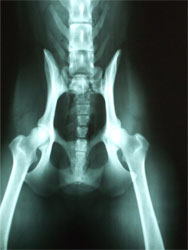

Imagiologia / Ecografia / Raio X